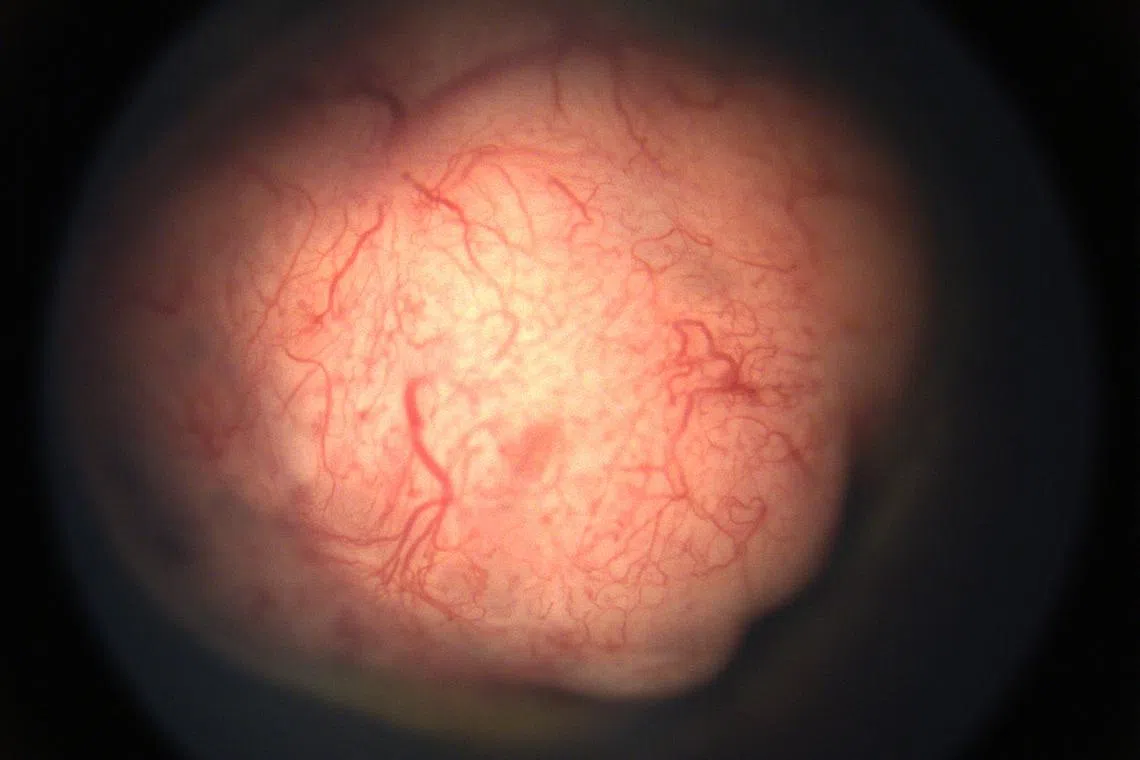

A retinoblastoma tumour growing in the eye.

PHOTO: SINGAPORE NATIONAL EYE CENTRE